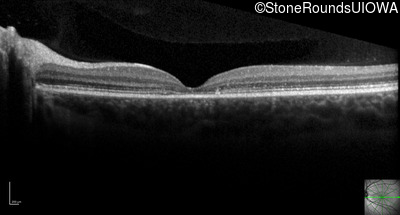

Optical Coherence Tomography - Right - 20/32

Exemplar / OCT Stack